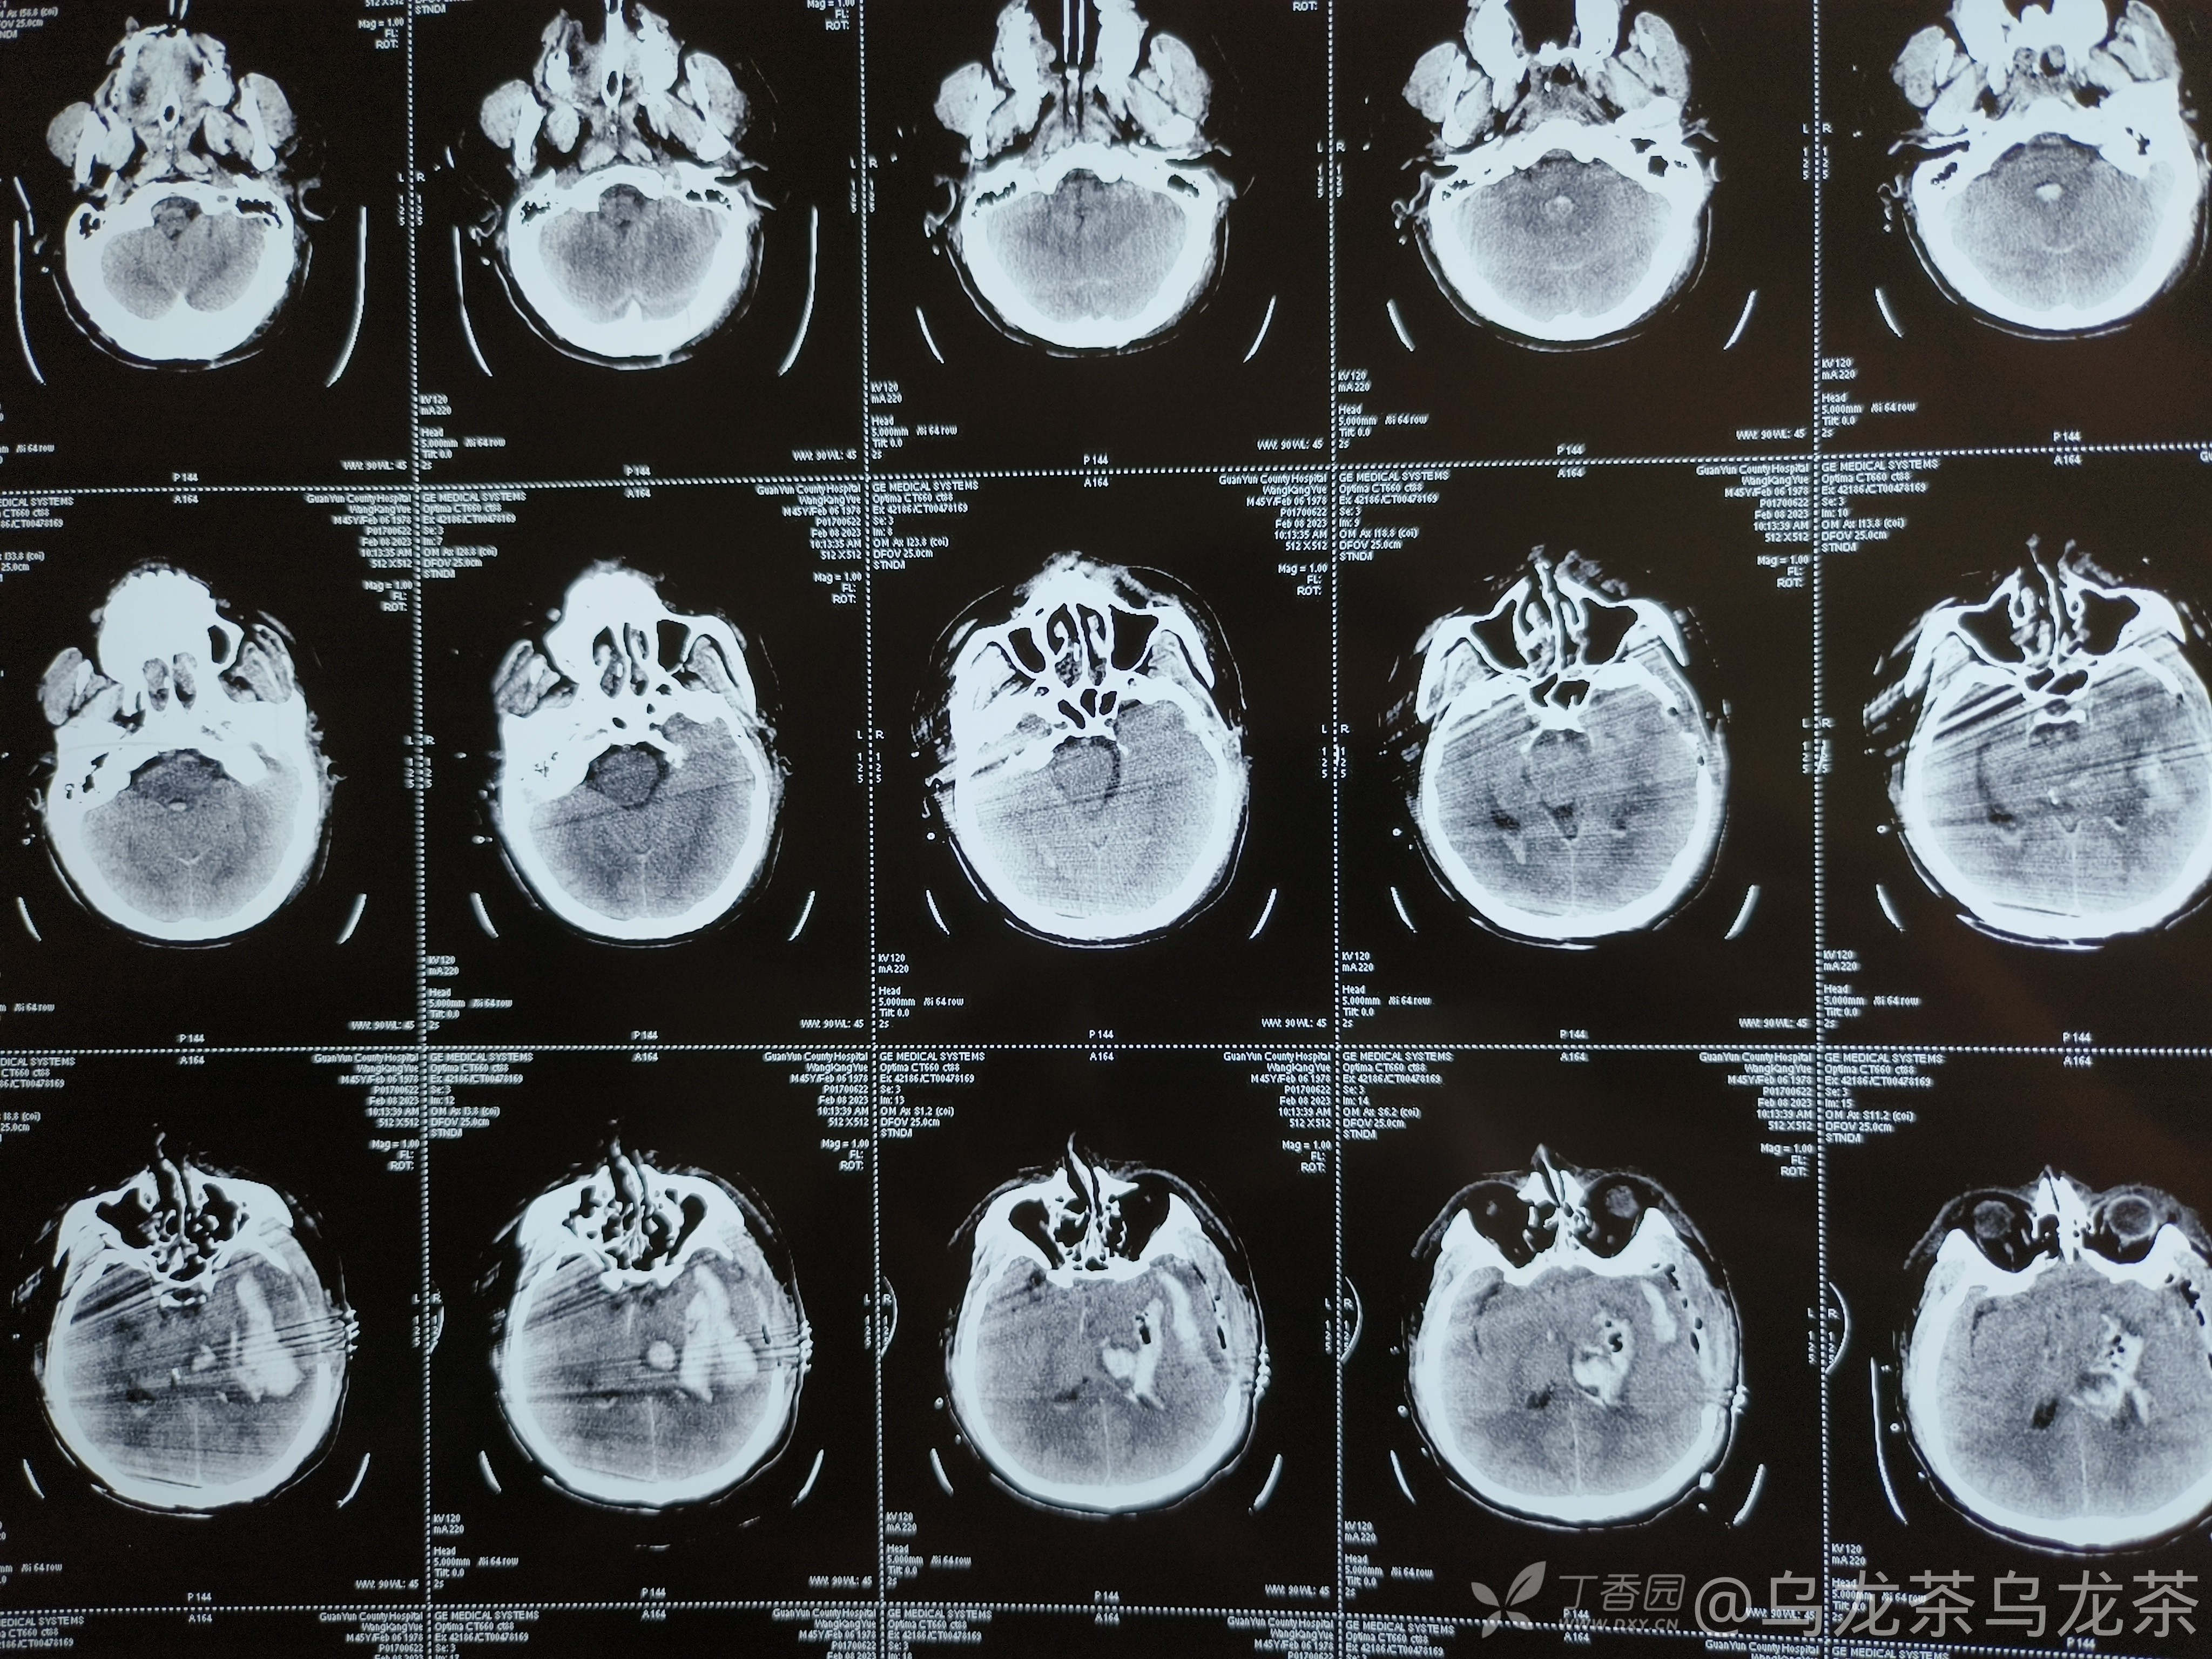

患者男,46岁,长期高血压病史,间断服药,平时未检测血压。三周前突发昏迷,送至我院就诊,查血压240/150mmhg,急查头颅ct如图

予急诊手术,术后三天复查ct

后于iuc行对症治疗,术后一周复查ct